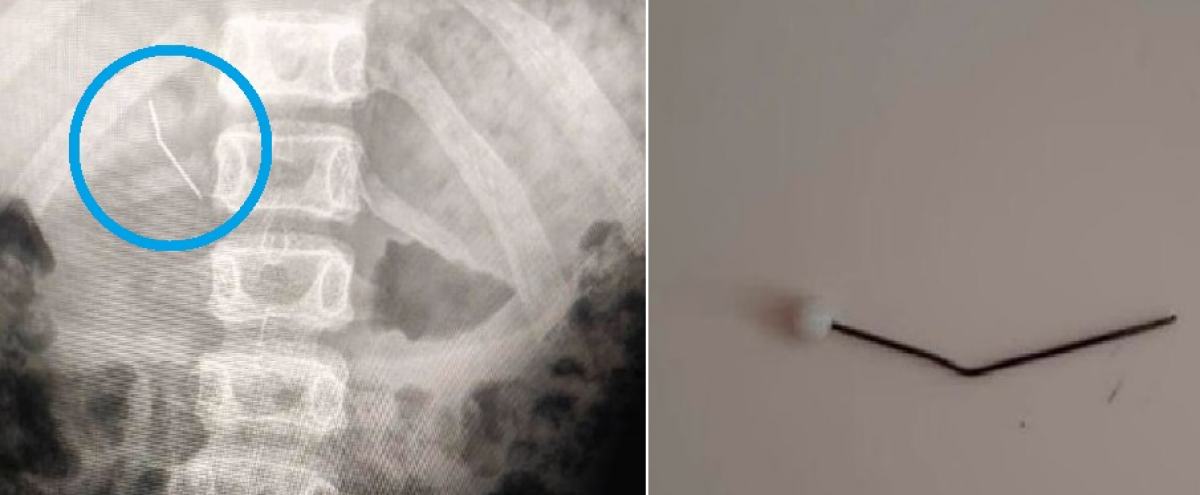

В Каражале ребенка осмотрел хирург, а затем направил его в КГП “Многопрофильная больница города Жезказган”. Обзорная рентгенография подтвердила наличие инородного тела в желудочно-кишечном тракте, – сообщают в управлении здравоохранения Карагандинской области.

Врачи извлекли английскую иглу за считанное время. Сейчас жизни ребенка ничего не угрожает. Пациенту рекомендовали наблюдаться у детского хирурга по месту жительства.